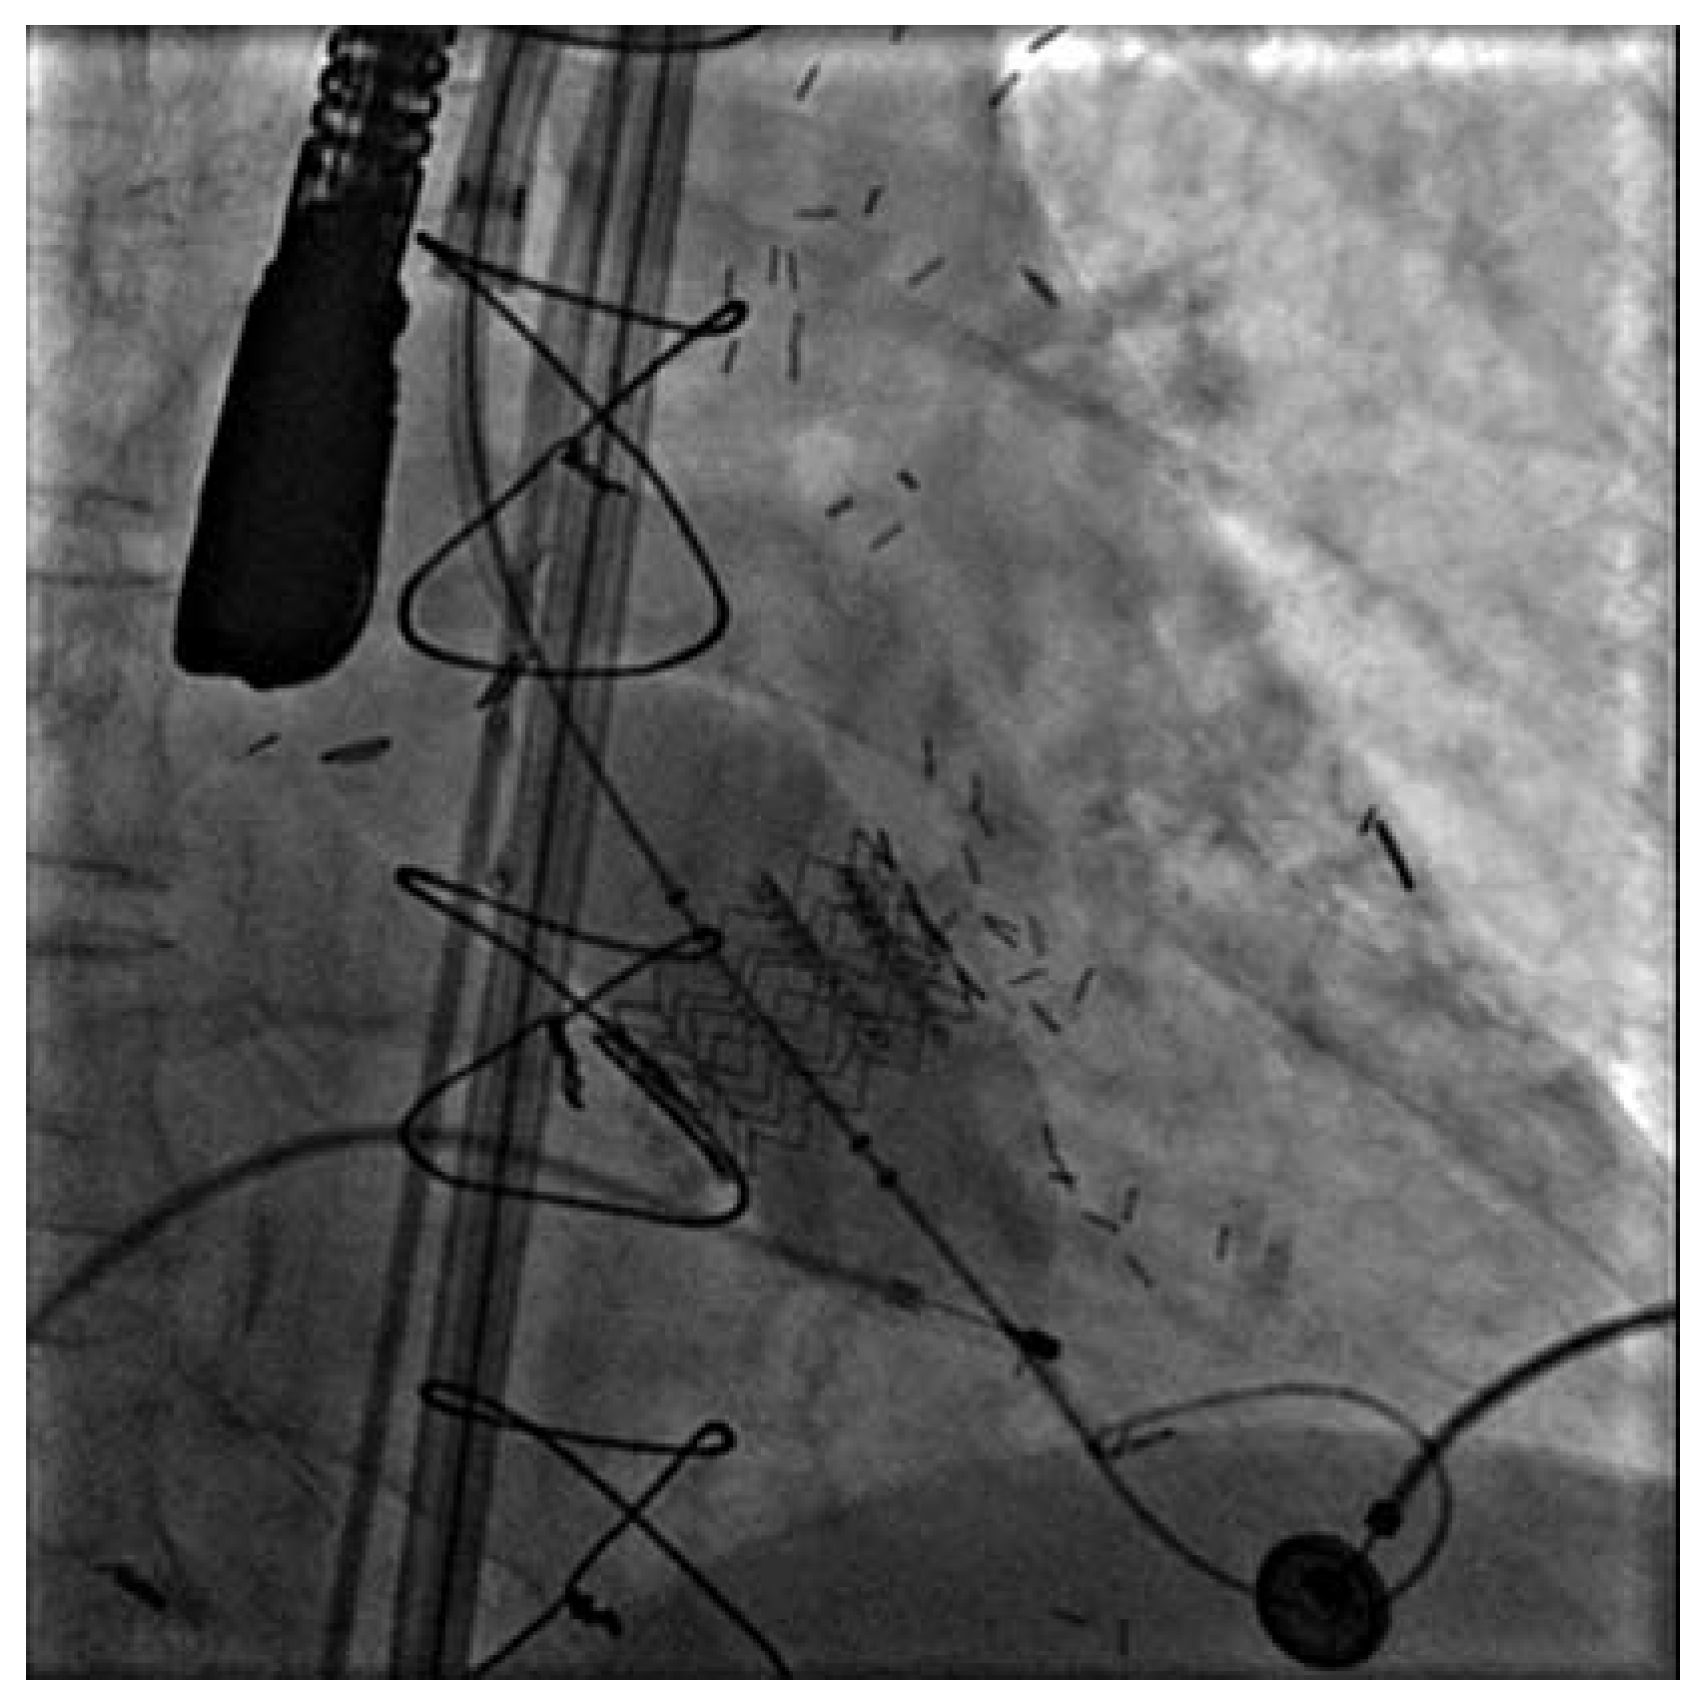

Figure 4. Karotisstenting USZ Kardiologie—Angiologie 2003–2006.

Schliesslich entwickelte sich das Karotis-Stenting zu einem bedeutenden Eingriff für interventionelle Kardiologen. Neue Technologien besonders durch Verwendung von so genannten Filter-Devices zur Vermeidung von zerebrovaskulären Embolien aus rupturierten Plaques haben die Ergebnisse erheblich verbessert. Am UniversitätsSpital Zürich wurden in den letzten Jahren über 140 solche Eingriffe mit einer minimalen Komplikationsrate (30-Tage-Mortalität-, Herzinfarkt- und Schlaganfall-Risiko 2,1%) auch bei Hochrisikopatienten durchgeführt (Figure 3 and Figure 4). Diese Ergebnisse machen deutlich, dass sich das Karotis-Stenting heute zu einer Alternative der Karotis-Endarterektomie entwickelt hat.